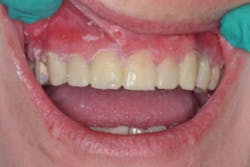

Finally, the moment of truth came. I looked to the ceiling, then to my assistant, and said, “Please work.” I popped the matrix off the teeth and ... behold ... teeth! See Figure 6.

At the post-operative visit two weeks later, the contacts were perfect, and I achieved anterior disclusion in all excursions. No other refinement of the restorations was needed other than polishing of the surfaces, which required minimal effort. Activa has a chameleon effect that blends shades and reflects adjacent hues to create a natural esthetic.